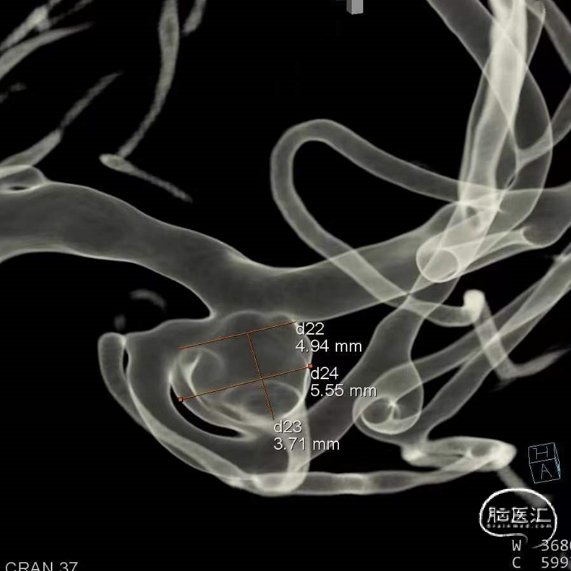

动脉瘤平均宽度5.41mm, 最小高度为3.71mm,瘤颈约为4.94mm,使用WEB™ SL 6*3mm瘤内扰流装置进行栓塞治疗。